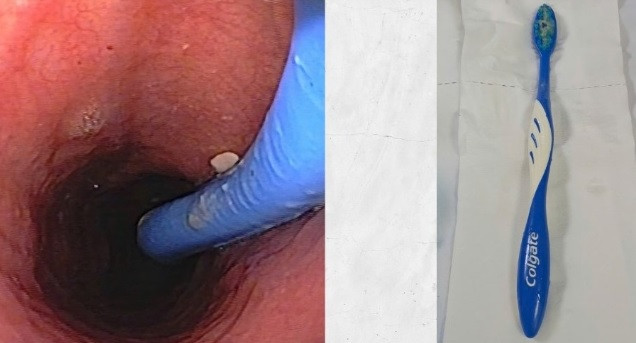

Người bệnh là nữ 30 tuổi ở (Thủy Nguyên, Hải Phòng). Sau bữa tối, người bệnh cảm thấy nghẹn ở họng, buồn nôn và nghi ngờ có vật cản. Thay vì đến bệnh viện, chị tự dùng bàn chải đánh răng để “giải cứu”… chính mình. Kết quả, chị vô tình nuốt trọn luôn chiếc bàn chải dài 17cm vào trong thực quản.

May mắn thay, chỉ khoảng 1 tiếng sau, người bệnh được đưa đến Bệnh viện Hữu nghị Việt Tiệp. Tại đây, đội ngũ nội soi tiêu hóa đã kịp thời can thiệp và lấy ra thành công dị vật nguyên vẹn, đảm bảo an toàn tuyệt đối cho người bệnh.

| Ca nội soi lấy dị vật bàn chải đánh răng cho bệnh nhân - Ảnh BVCC |

| Chiếc bàn chải đánh răng trong thực quản bệnh nhân và sau khi được lấy ra - ảnh BVCC |